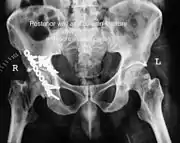

Axial CT image (viewed on bone windows) of a complex comminuted left acetabular fracture involving both anterior and posterior columns.

Fracture of the acetabulum